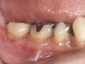

このようにして移植された歯は、歯の根の表面にある歯根膜と言う組織がほぼ完全に保存され、生着(生きた状態で移植されて機能する事)する事によって、将来矯正治療で歯を移動する事もできますし、被せもの等を行えば全く移植歯である事は気が付かれないレベルで仕上がります。

根管治療の終了後は、被せものをして、治療は終了となり、メインテナンスに移行して行きます。